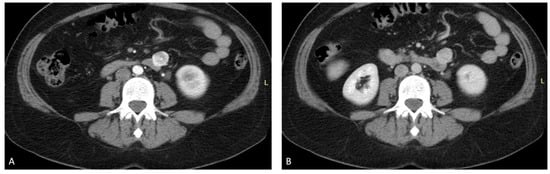

2.1. Abdominal and Pelvic CT with Contrast